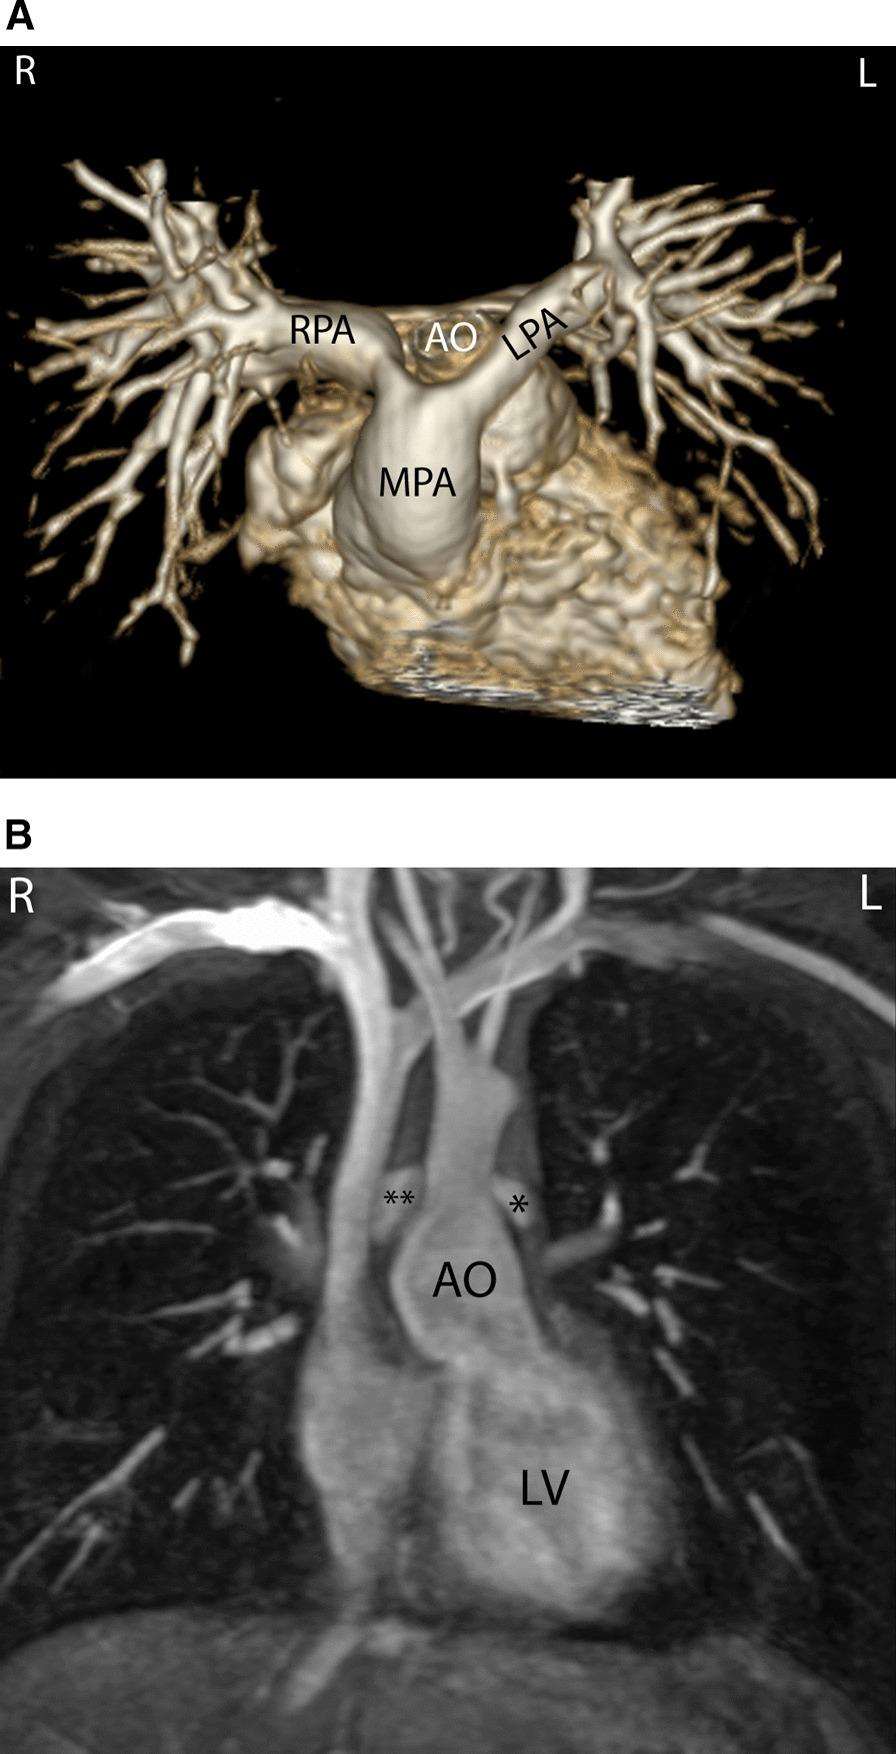

Cardiovascular magnetic resonance (CMR) has been utilized in the management and care of pediatric patients for nearly 40 years. It has evolved to become an invaluable tool in the assessment of the littlest of hearts for diagnosis, pre-interventional management and follow-up care. Although mentioned in a number of consensus and guidelines documents, an up-to-date, large, stand-alone guidance work for the use of CMR in pediatric congenital 36 and acquired 35 heart disease endorsed by numerous Societies involved in the care of these children is lacking. This guidelines document outlines the use of CMR in this patient population for a significant number of heart lesions in this age group and although admittedly, is not an exhaustive treatment, it does deal with an expansive list of many common clinical issues encountered in daily practice.

心血管磁共振(CMR)在儿科患者的管理和护理中已经应用了近 40 年。它已经发展成为评估最小的心脏的宝贵工具,用于诊断、介入前管理和随访。尽管在许多共识和指南文件中提到,但在儿科先天性心脏病和后天性心脏病领域,目前还缺乏一份由众多参与儿童护理的学会共同认可的、最新的、独立的、针对 CMR 使用的大型指南。本指南文件概述了 CMR 在该年龄段的许多心脏病变中的应用,尽管不能说是详尽的治疗方法,但它确实涉及了在日常实践中经常遇到的许多常见临床问题的广泛列表。